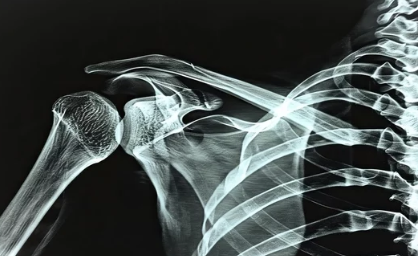

- 영상 검사: X-ray, 초음파, MRI 등 영상 검사를 통해 뼈, 연골, 힘줄, 인대 등의 상태를 확인하고 정확한 진단을 내립니다.